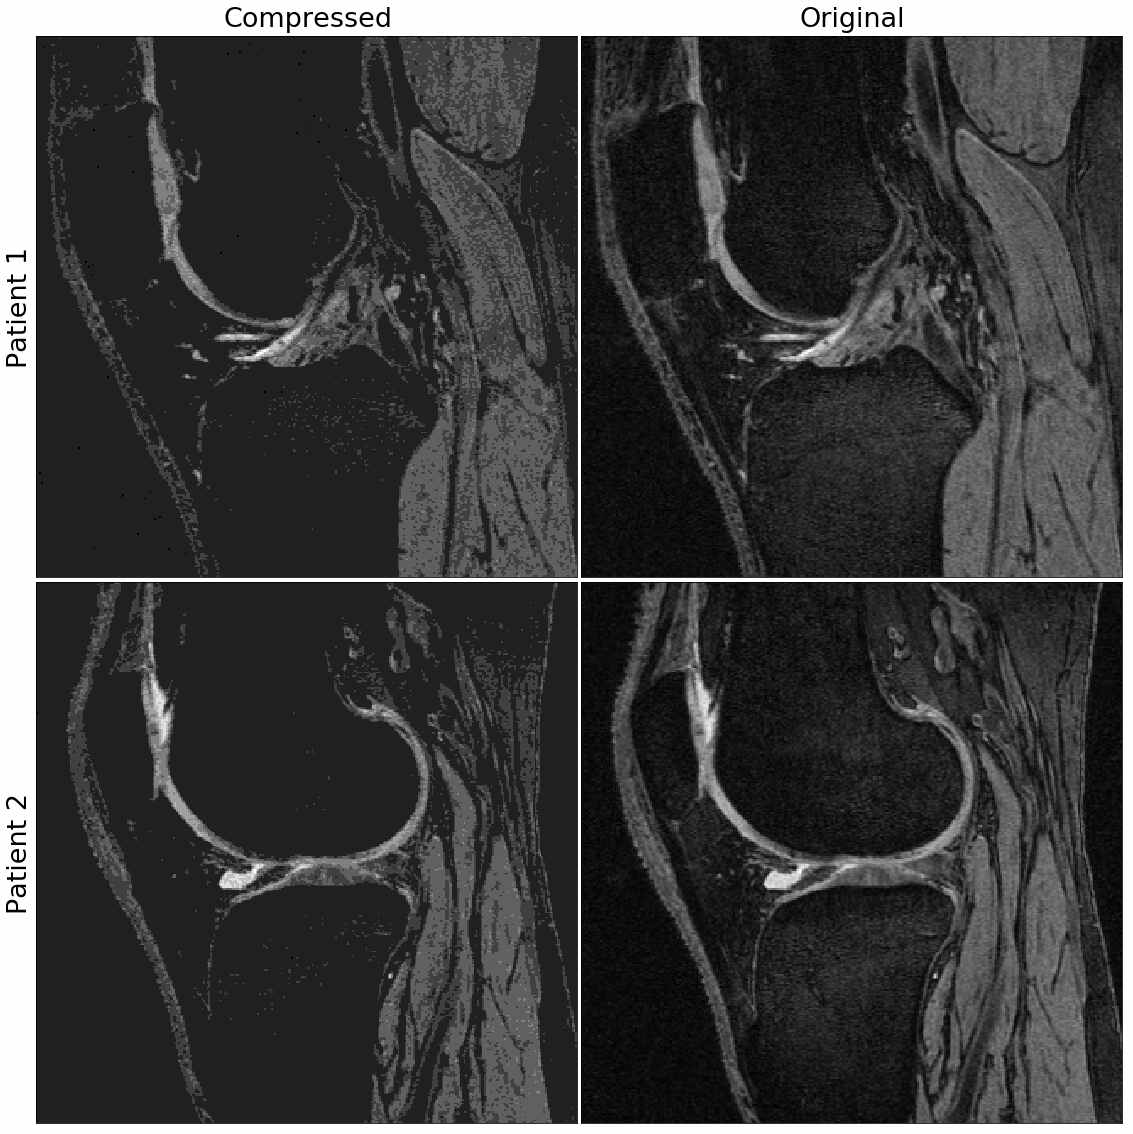

Precision in Knee MRI Improved Pathology Visualization Mri With Total Knee Replacement The good news is that it is usually safe to get an mri after joint replacement surgery. In partial knee replacement such as patellofemoral replacement (pfr) or unicondylar knee replacement (ukr), the metallic burden for imaging is lower. On the other hand, preserved compartments can deteriorate with time, and. However, there are some precautions that need to be taken. Total. Mri With Total Knee Replacement.